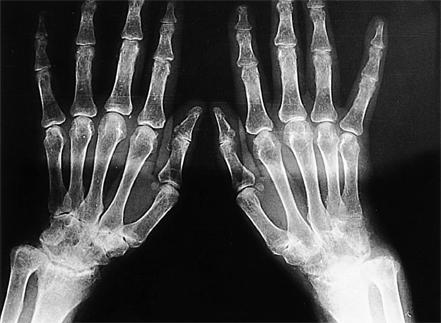

Femoral mononeuropathy (FMN) as an extraarticular finding of rheumatoid arthritis (RA) is a phenomenon which has not been reported previously. We report a 53-year-old female patient with RA, presenting FMN findings during the course of the disease. On examination, right quadriceps and iliopsoas muscles showed grade 3 weakness on the Medical Research Council (MRC) scale. Sensory examination revealed sensory loss in the right medial leg and thigh. Patellar tendon reflex was absent in the right side. A diagnosis of a partial right femoral neuropathy was confirmed using nerve conduction study and electromyography. The probable mechanism of FMN was thought to be vasculitis.